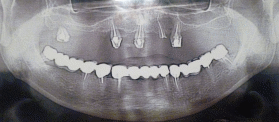

21. Ортопантограмманы оқығаннан кейін ауыз қуысын имплант арқылы протездеуге тиімді хирургиялық дайындық жоспарын құрыңыз:

бірден имплантация

біркезеңдік имплантация

синус лифтингсіз имплантация

синус лифтинг (ашық,жабық)+

имплантатты 6-8 айдан кейін орнату

22.Науқас 48 жаста рентгенологиялық тексеруден кейін оң жақтағы жоғарғы жақ қуысы тұсында альвеолярлы өсіндінің биіктігі мен қалыңдығы 6 мм анықталды.

Барлық көрсетілген имплантация жоспарлары дұрыс біреуінен БАСҚАСЫ .

жабық синус лифтинг бір кезеңдік имплантациямен

ашық синус лифтинг бір кезеңдік имплантациямен

гайморотомия+

ашық синус лифтинг, имплантатты 6-8 айдан кейін орнатумен.

жабық синус лифтинг, имплантатты 6-8 айдан кейін орнатумен.

23.Жоғарғы жақ қуысын рентгендік тексеруден кейін жоғарғы жақ қуысының тұсында альвеолды өсіндінің биіктігі 15 мм, ені 9мм.

Имплантацияның ең ТИІМДІ түрін таңдаңыз.